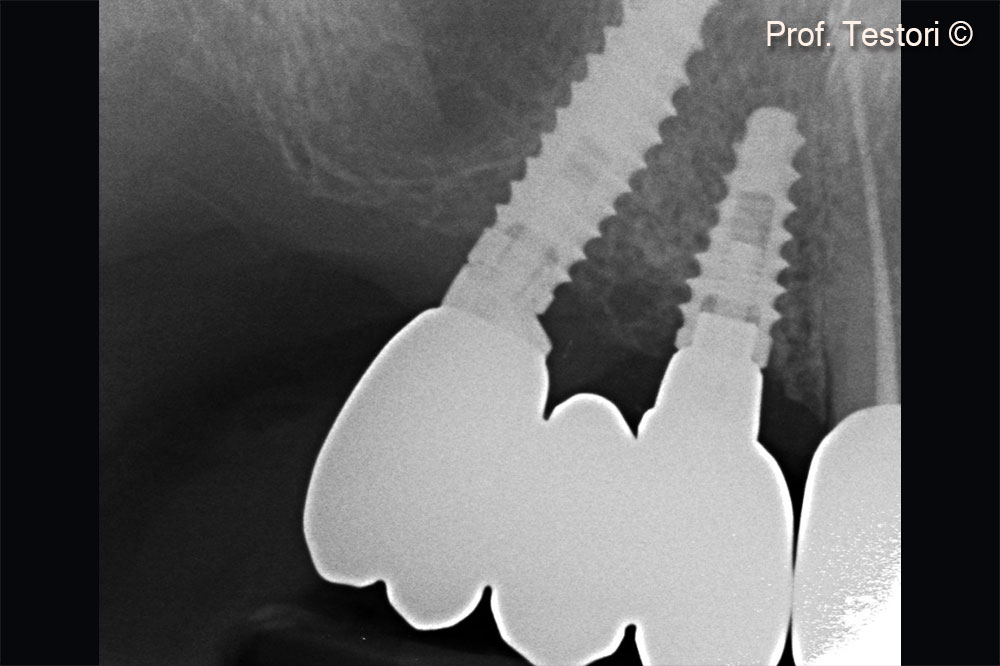

Peri-apical x-ray at definitive crown delivery after 4 months.